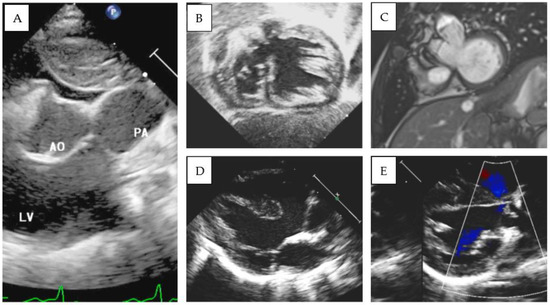

Patient 4 was transferred from another center because of severe cyanosis (SpO2 40%). On admission, S,D,L-DOLV with subaortic VSD and PS were diagnosed. The aorta was anterior and to the left of the pulmonary artery and overrode a large conoventricular VSD. The pulmonary valve annulus was hypoplastic, and posterior deviation of the infundibular septum was evident. The mitral valve showed fibrous continuity with the pulmonary artery, and a well-developed subaortic conus was detected in 2D echocardiography (Figure 3D,E). A balloon atrial septostomy was performed to increase blood mixing, and the baby was then discharged. REV (Reparation à l’ètage ventriculaire) was performed at 1 year of age. After a follow-up period of 8.6 years, the patient showed a good clinical status. Significant pulmonary regurgitation was present at cardiac follow-up MRI (regurgitant fraction: 49%) with a mild increase in right ventricular volumes (end-diastolic volume 103 mL/m2). During periodic Holter monitoring, no significant arrhythmia was identified, except for the finding of ectopic atrial rhythm, without significant symptoms and with adequate chronotropic response during exercise stress testing.

Figure 3.

(A) 2D Echocardiographic parasternal short-axis view documenting both great arteries originating from the morphological left ventricle. (B) Echocardiographic and (C) MRI views documenting DOLV and hypoplasic right ventricle (patient 1). (D,E) Parasternal long-axis view documenting mitro-aortic discontinuity and mitro-pulmonary continuity in patient 4.